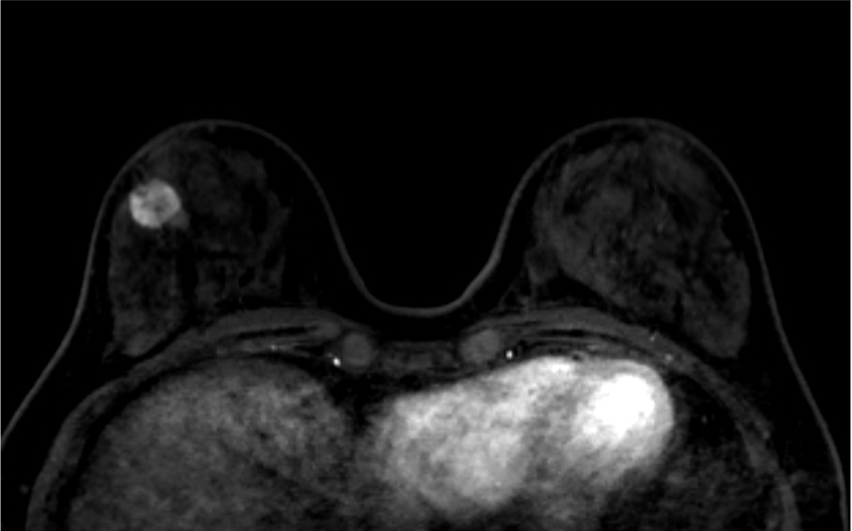

4. ダイナミックMRI (造影前 早期相 遅延相)

早期相で、乳腺の辺縁にBPE(矢印)を認めるが、その範囲は広くなくmildと判定する。乳癌の病変は、早期相から急速に造影され、遅延相でwash outがみられる。BPEは、遅延相で拡大し増強している。

5. Ultrafast DCE

乳癌の病変は、超早期(10相目: 造影剤注入32.5秒後)から急速に造影されている。背景乳腺は超早期では、ほとんど造影されていないが、17相目では軽度増強されている。